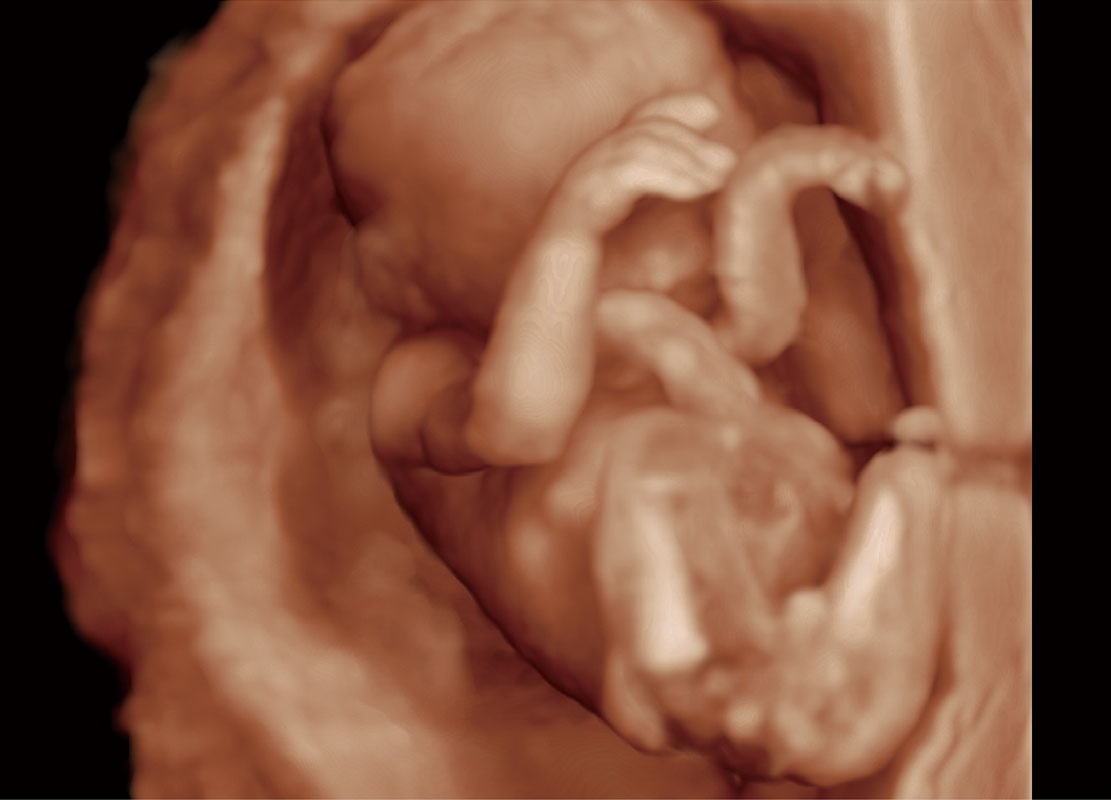

高分辨率容积成像-早孕胎儿

光影成像-孕囊